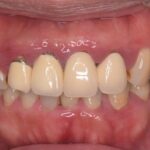

ダイレクトボンディングなどの

審美治療も高精度に対応

肉眼では見えない細かな部分まで拡大して確認できるため、削りすぎを防ぎ、再発リスクを抑えた質の高い治療が可能です。

治療だけでなく、歯科衛生士による予防・メンテナンスにもマイクロスコープを活用し、細部まで丁寧にケアを行っています。